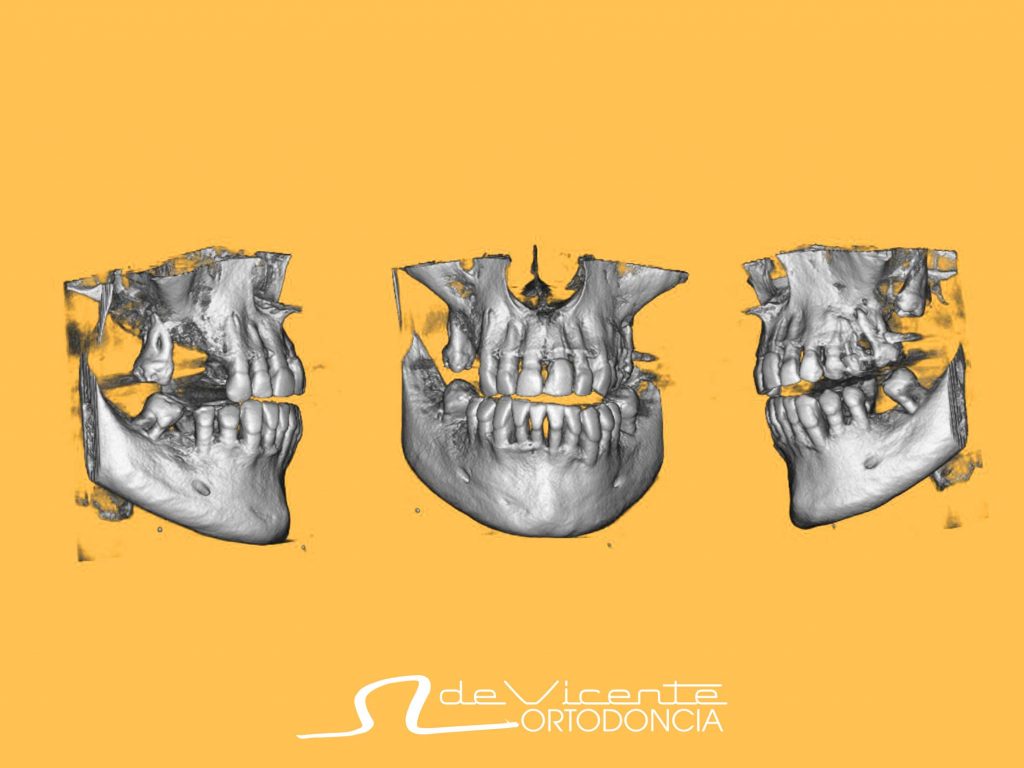

El nuevo aparato del que disponemos en la clínica dental De Vicente Ortodoncia es un CBCT o también llamado tomografía computarizada de haz cónico. Se parece a un TAC convencional y nos permite ver en 3 dimensiones los tejidos duros del paciente, es decir, principalmente el hueso y los dientes. Es similar a una radiografía pero en 3D. Sin embargo, utiliza menos radiación, con unos resultados a nivel de definición y calidad muy altos.

El CBCT permite estudiar al paciente en tres dimensiones, no en dos, como el resto de los aparatos. Es decir, no solo altura y longitud, si no también anchura o profundidad. Nos da mucha información diagnóstica, que de otra forma pasaría desapercibida. Además, el nivel de radiación que presenta es pequeño y personalizable, lo que lo hace muy seguro para los pacientes.

Se utiliza en todos aquellos casos en donde queremos ver y entender la situación tridimensional del paciente. Nos permite entender la anchura o altura del hueso, donde esta la posición de algunas estructuras nobles como nervios o senos maxilares, así como saber exactamente la posición de dientes respecto al hueso y a dichas estructuras, así como su posición.

Con toda la información, la cavidad oral del paciente se puede visualizar de forma digital. Ya tenemos la situación exacta de la boca, incluyendo el hueso, nervios, dientes… en el ordenador. Eso hace que todos los tratamientos puedan ser correctamente estudiados, analizados, diseñados, y en resumen, que podamos otorgar la mayor calidad posible y seguridad a nuestros pacientes.